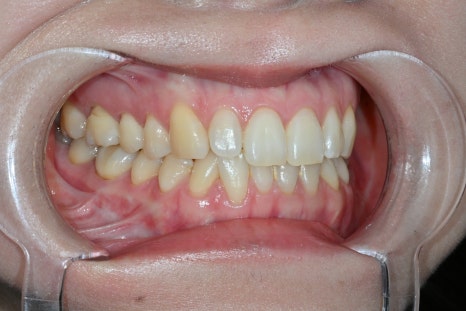

Changes after treatment

<BEFORE>

<AFTER>

After treatment, the patient experienced

a natural smile

a softer change in impression

greater satisfaction in photos

In particular, there were many comments like

"I can't tell that they had laminates"

"It just feels like they became prettier."

This is exactly the result of

Obzero Pure Laminates.